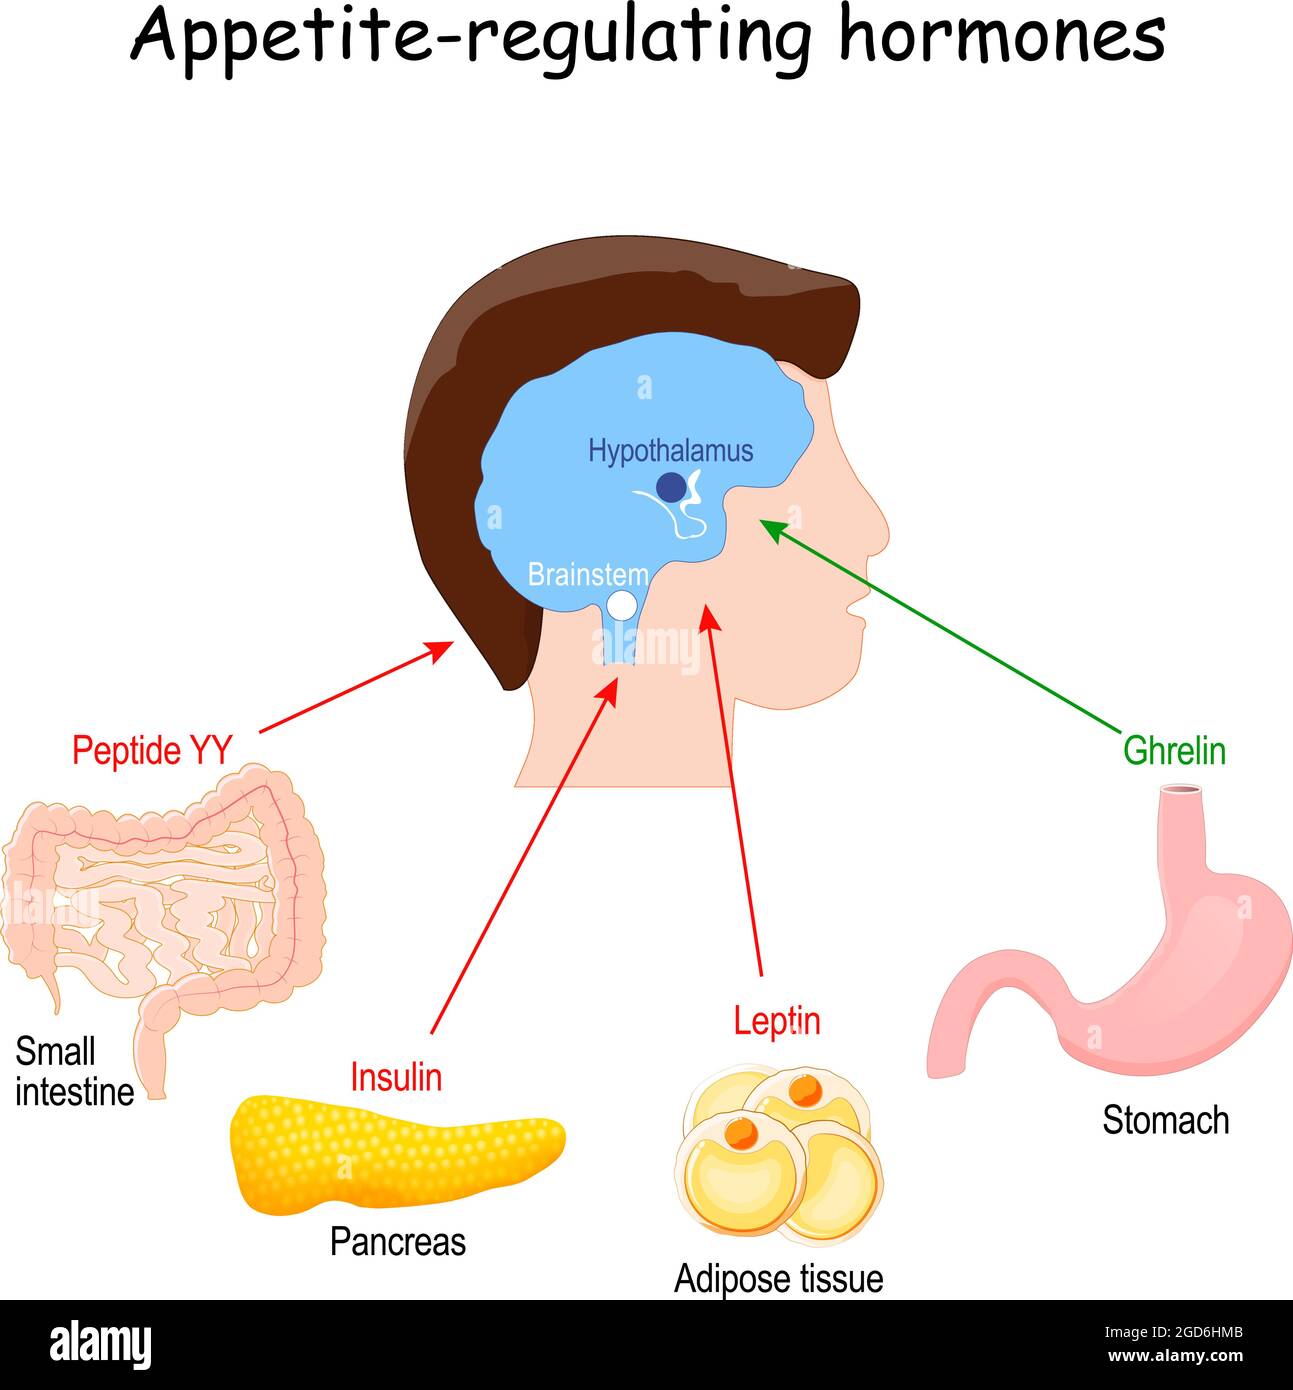

RF2GD6HMB–Leptine, ghréline, insuline et peptide YY. Hormones qui régulent le métabolisme, l'appétit, la satiété et la faim. Illustration vectorielle